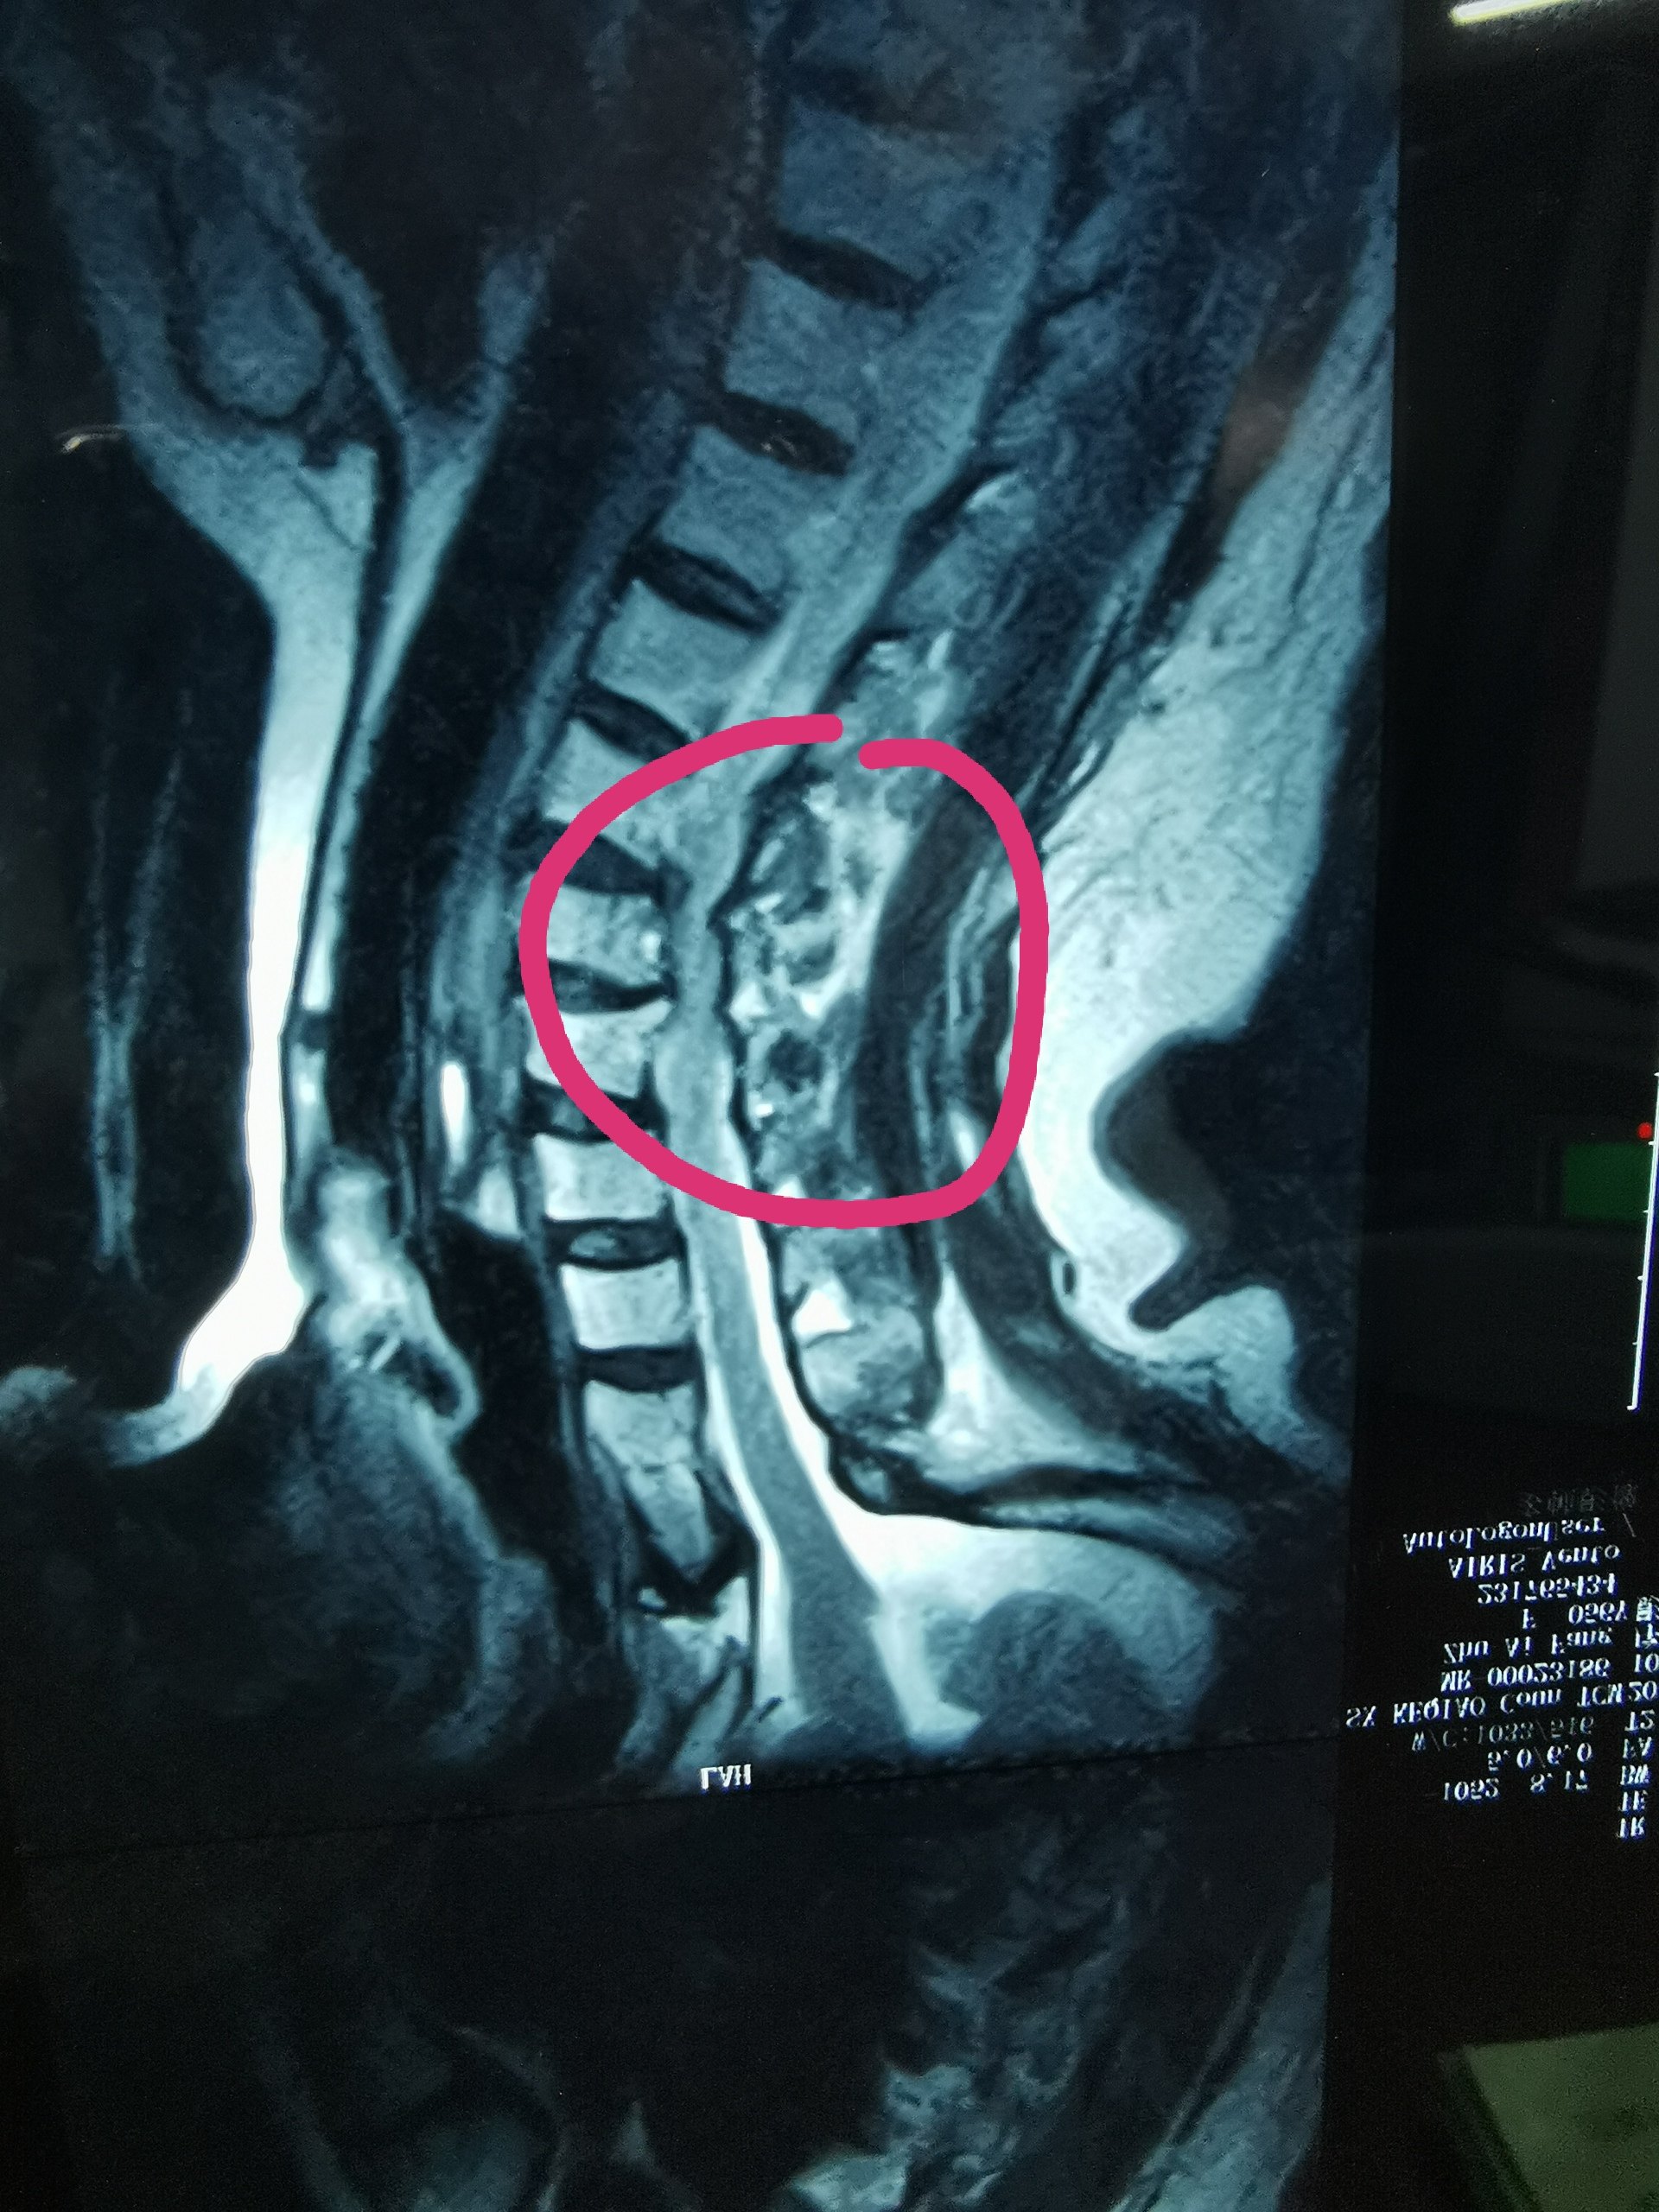

颈椎间盘突出症全称为“腰椎间盘纤维环断裂、髓核脱出症”腰椎间盘突出症的锻炼方法图片,主要是因为颈椎间盘的骨膜板、纤维环及髓核三部份随着年纪的下降出现了颈椎间盘退行性肿瘤,致使其渐渐丧失柔硬度、弹性以及避震的功能,而该部位自身修补能力较差。在外力诱因的作用下,颈椎间盘的纤维环极易出现断裂,造成髓核组织从纤维环断裂的地方突出,使得相邻的脊神经根遭到相应的剌激或压迫,因而形成臀部肿胀、下肢肿胀等一系列临床病症。

颈椎间盘突出症病人容易出现病况反复,因而不仅放疗医治、药物医治、牵引医治、物理医治、针灸疗法、推拿疗法等以外,功能锻练也十分重要。